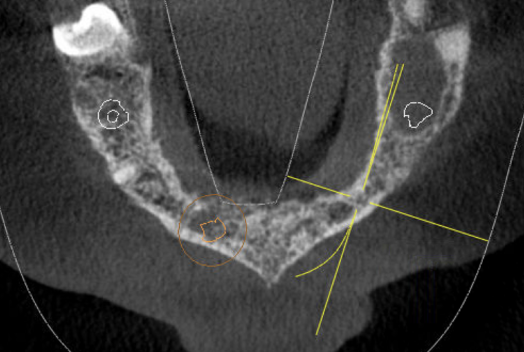

GREFFE OSSEUSE SOUS SINUSIENNE ET RECONSTRUCTION DE CRETE EN EPAISSEUR

AVANT APRES RECONSTRUCTION OSSEUSE HORIZONTALE

AVANT APRES ELEVATION OSSEUSE SOUS-SINUSIENNE